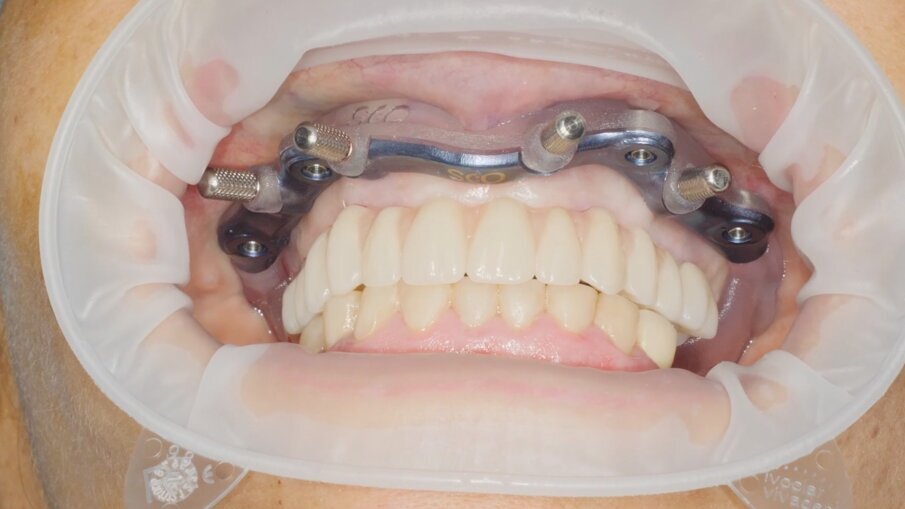

Veniamo quindi al posizionamento della protesi mediante carrier, a sua volta ancorato agli stessi punti di fissaggio della dima base. È significativo osservare come la stabilizzazione della sola vite palatale consenta l’allineamento perfetto tra i sistemi di fissaggio (Fig. 22), mentre il dettaglio mostrato in Fig. 24 illustra efficacemente come prima della cementazione della protesi l’accoppiamento e la centratura del foro protesico appaiano perfetti, confermando quindi come l’obiettivo di alloggiamento della protesi nella sede prestabilita sia stato colto. Per la fase di cementazione con cemento duale si è prestata attenzione alla realizzazione di un foro aggiuntivo per permettere al materiale di raggiungere gli abutment. I fori di accesso alle viti vengono tappati con filo di teflon (Figg. 25, 26) ed è a questo punto possibile andare a fissare la protesi e rimuovere il sistema carrier (Fig. 27). Lasciamo la dima in posizione, così che nell’eventualità in cui un abutment non dovesse essere stato cementato correttamente, ci riserviamo la possibilità di riprendere il posizionamento strategico dell’intero sistema Pcube, intercettando possibili impedimenti alle manovre di finalizzazione del caso.

Nella fase di controllo finale possiamo apprezzare come i rapporti di intercuspidazione programmati siano stati perfettamente rispettati (Fig. 28), senza necessità di ricorrere a procedure di auto-centratura della protesi, grazie ad una attenta pianificazione digitale. Eseguiamo una scansione con scan abutment in posizione prima di procedere con la rimozione della dima base e il fissaggio della protesi (Figg. 29-31). Controlliamo le possibilità di mantenimento igienico tenendo conto che, trattandosi di un intervento flapless, non abbiamo le problematiche legate alla gestione di una linea di incisione (Fig. 32). La Fig. 33 mostra la corretta guarigione dei tessuti quindici giorni dopo il trattamento. Eseguiamo un controllo radiografico mirato a verificare il corretto alloggiamento di tutti gli impianti e della protesi (Fig. 33), dove possiamo vedere la struttura di rinforzo in fibra di vetro.

Fig. 28